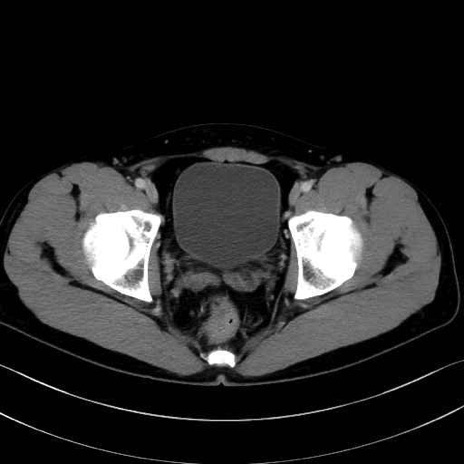

恥骨筋(pubic muscle) のCT画像の解剖

恥骨筋 (Pectineus)